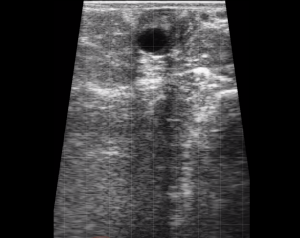

SIMON Ultrasound Database

This ultrasound database is a free resource for students and doctors!

Our collection includes videos of dogs, cats, horses, cows, humans, and many other species!